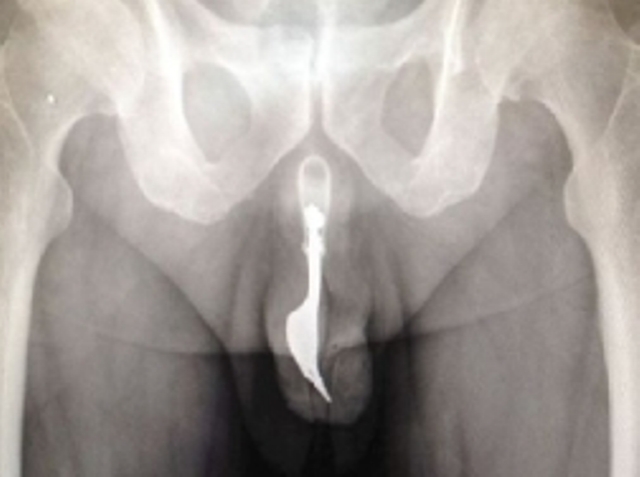

Sipas artikullit 60 vjeçari u paraqit në ndihmën e shpejtë të spitalit të Cambera, me organin gjenital të larë në gjak, pasi kishte futur pirunin për të stimuluar kënaqësinë seksuale.

Në artikullin e publikuar në “International Journey of Surgery”, thuhej se burri kishte futur pirunin e gjatë rreth 10 cm, dymbëdhjetë orë më parë, por nuk arrinte më ta hiqte.

Mjekët u shprehën se ky ishte rasti i parë i kësaj natyre që trajtonin, duke e futur me urgjencë në kirurgji, duke përdorur lubrifikues dhe pinca të posaçme, ndërsa pacienti ndodhej në anestezi totale.